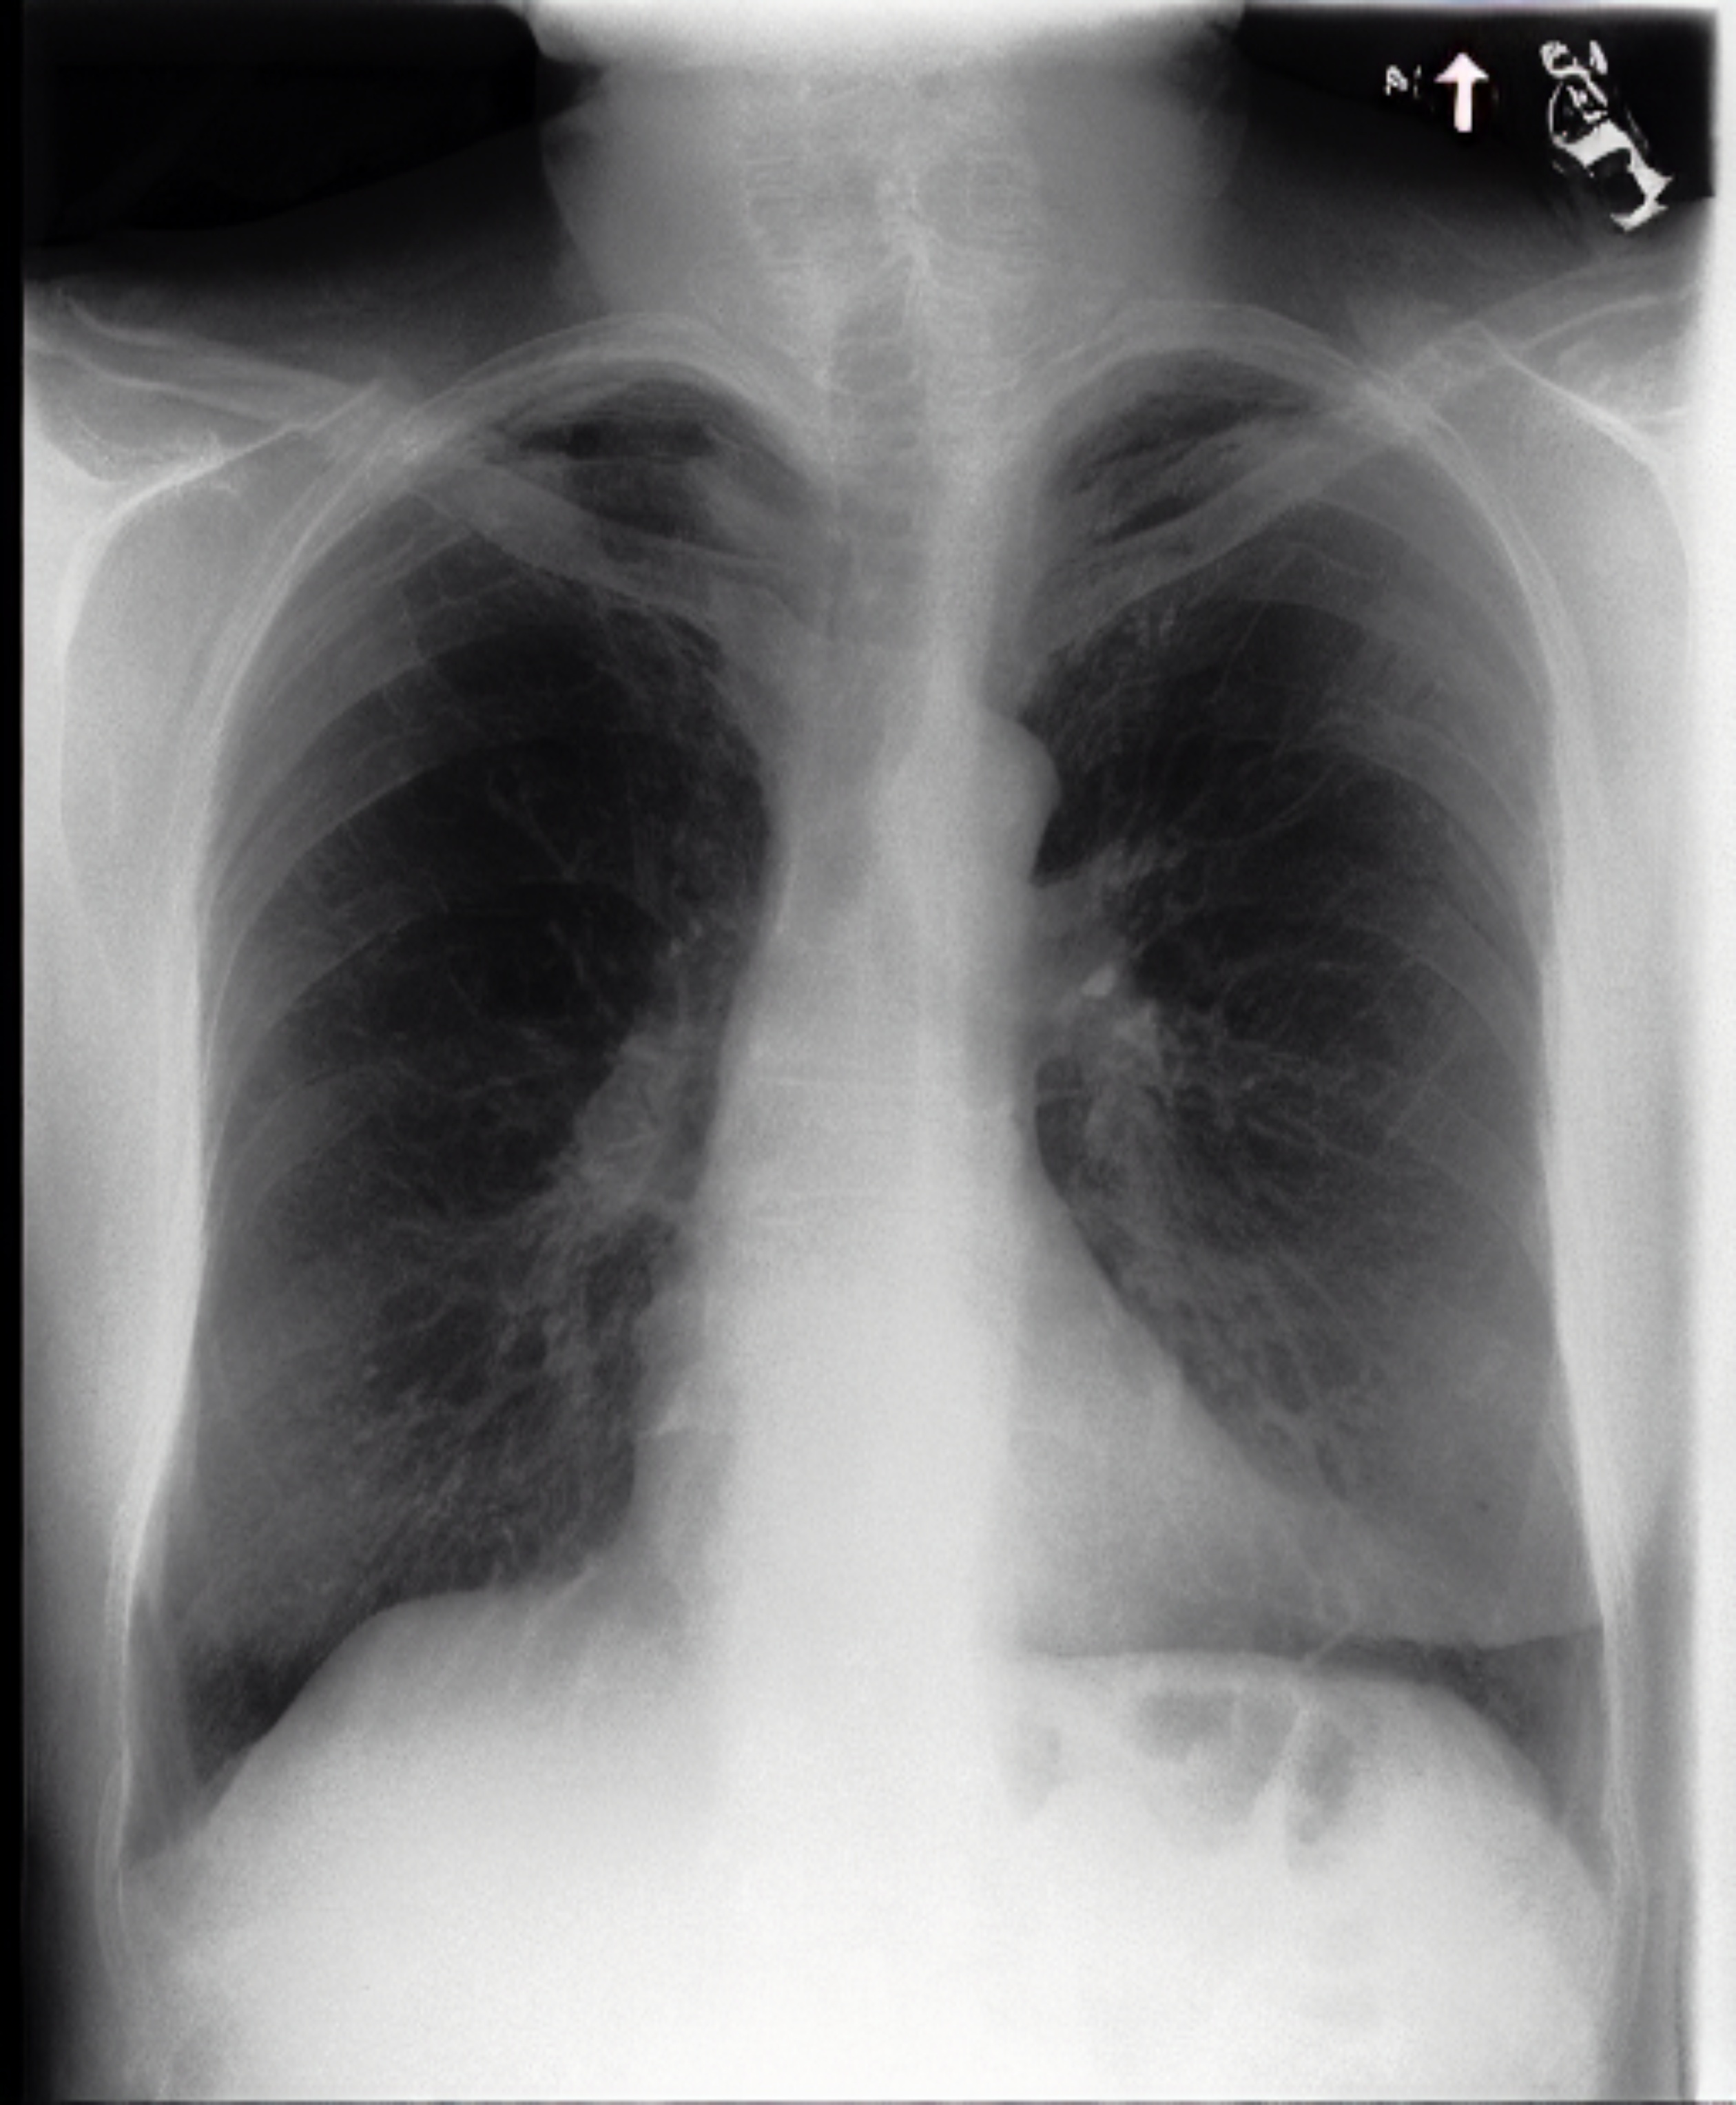

Table 1: Sample chest X-ray (CXR) images. The top row shows a normal CXR, while the remaining rows display CXRs with various pathologies, including right-sided cardiomegaly, large pneumothorax, viral pneumonia, and pulmonary edema.

Normal Chest X-ray Image

[Uncaptioned image]

Right-sided Cardiomegaly Large Pneumothorax

[Uncaptioned image] [Uncaptioned image]

Virus Pneumonia Pulmonary Edema